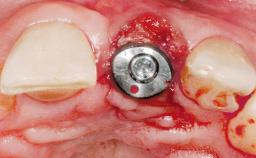

A 30-year-old female patient was referred to the office for the treatment of tooth 11. Her chief concern at the initial visit was to inquire, “Why is my tooth pink?” Upon clinical examination, it was determined that tooth 11 had a previous history of trauma and that the clinical crown had become noticeably pink in color as a result of internal resorption. This diagnosis was confirmed radiographically, indicating a large radiolucency involving the central and distal portions of the clinical crown. It was determined that restoration of this tooth was not possible, and that extraction was indicated. The presence of a mid-line diastema, which the patient wanted to reproduce, directed the treatment plan for tooth replacement utilizing a dental implant.

Type of Implants One-Piece|Reduced-Diameter

Bone Augmentation Horizontal|Simultaneous

Augmentation Materials Autogenous chips|Membrane

Placement Protocol Immediate implant placement

Tooth Site Maxillary incisor or canine

Socket Morphology Single-root socket

Socket Integrity Sufficient, with intact bone walls

Bone Volume Sufficient, with intact walls